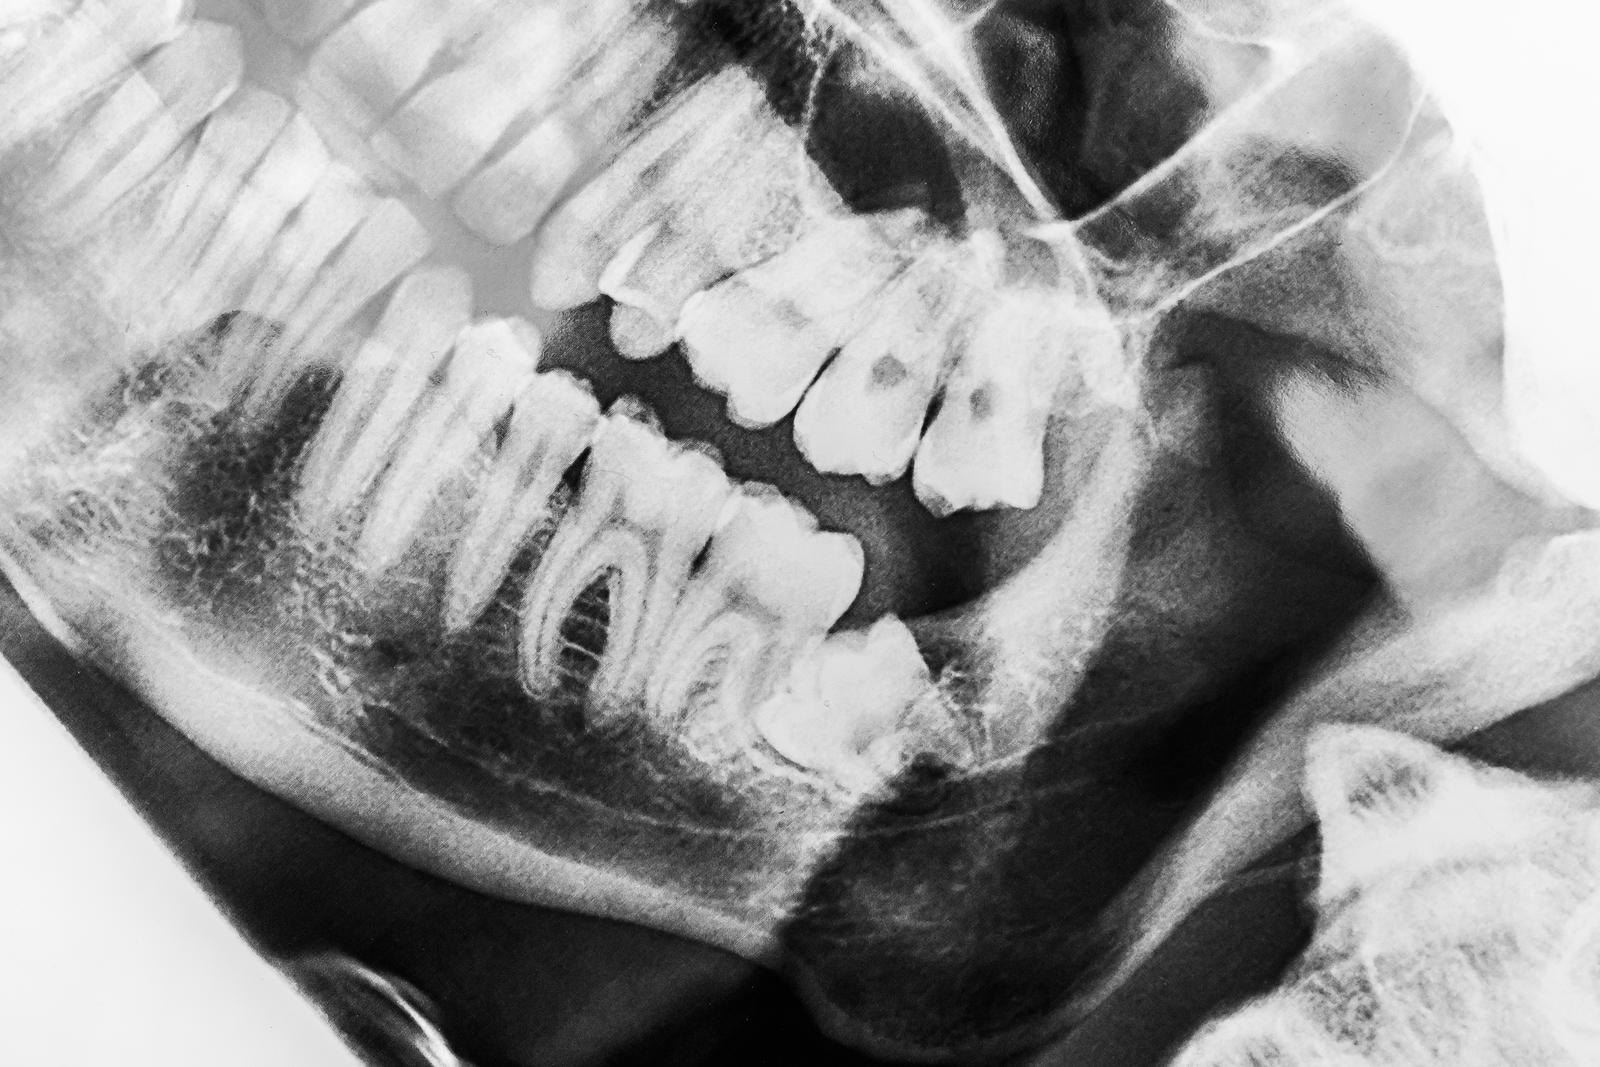

Ważne jest, aby przed przystąpieniem do ekstrakcji zęba mądrości odpowiednio się przygotować. Ma to znaczenie zarówno dla naszego zdrowia, jak i wykonania wszelkich niezbędnych badań. Do wykonania zabiegu niezbędne jest wykonanie zdjęcia panoramicznego, tomografii wolumetrycznej lub badania CBCT. Zdjęcia pantomograficzne wykonywane są w projekcji 2-D. Pokazuje to jednocześnie obszar szczęki i żuchwy. A CBCT jednak obraz konkretnych obszarów w projekcji trójwymiarowej. Pozwala to na większą precyzję i lepsze wyniki. Oba obrazy mogą określić lokalizację zęba, aby można było przeprowadzić leczenie. Obrazy te pokazują również relacje między zębem a otaczającymi go strukturami, takimi jak kanał nerwu zębodołowego dolnego. Dzięki temu dentysta z wyprzedzeniem może poznać trudność i przygotowanie wymagane do zabiegu.